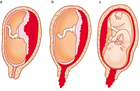

1. 常位早期剥離の初期症状は、切迫早産と極めて類似しているので注意を要する(推奨度2)

1. 性器出血、下腹痛、子宮収縮に異常胎児心拍パターンを認めた場合は常位胎盤早期剝離を疑う(推奨度2)

1. 腹部外傷では軽症であっても常位胎盤早期剝離を起こすことがあり、子宮収縮を認める場合では胎児心拍モニタリングで継続的に監視する(推奨度2)